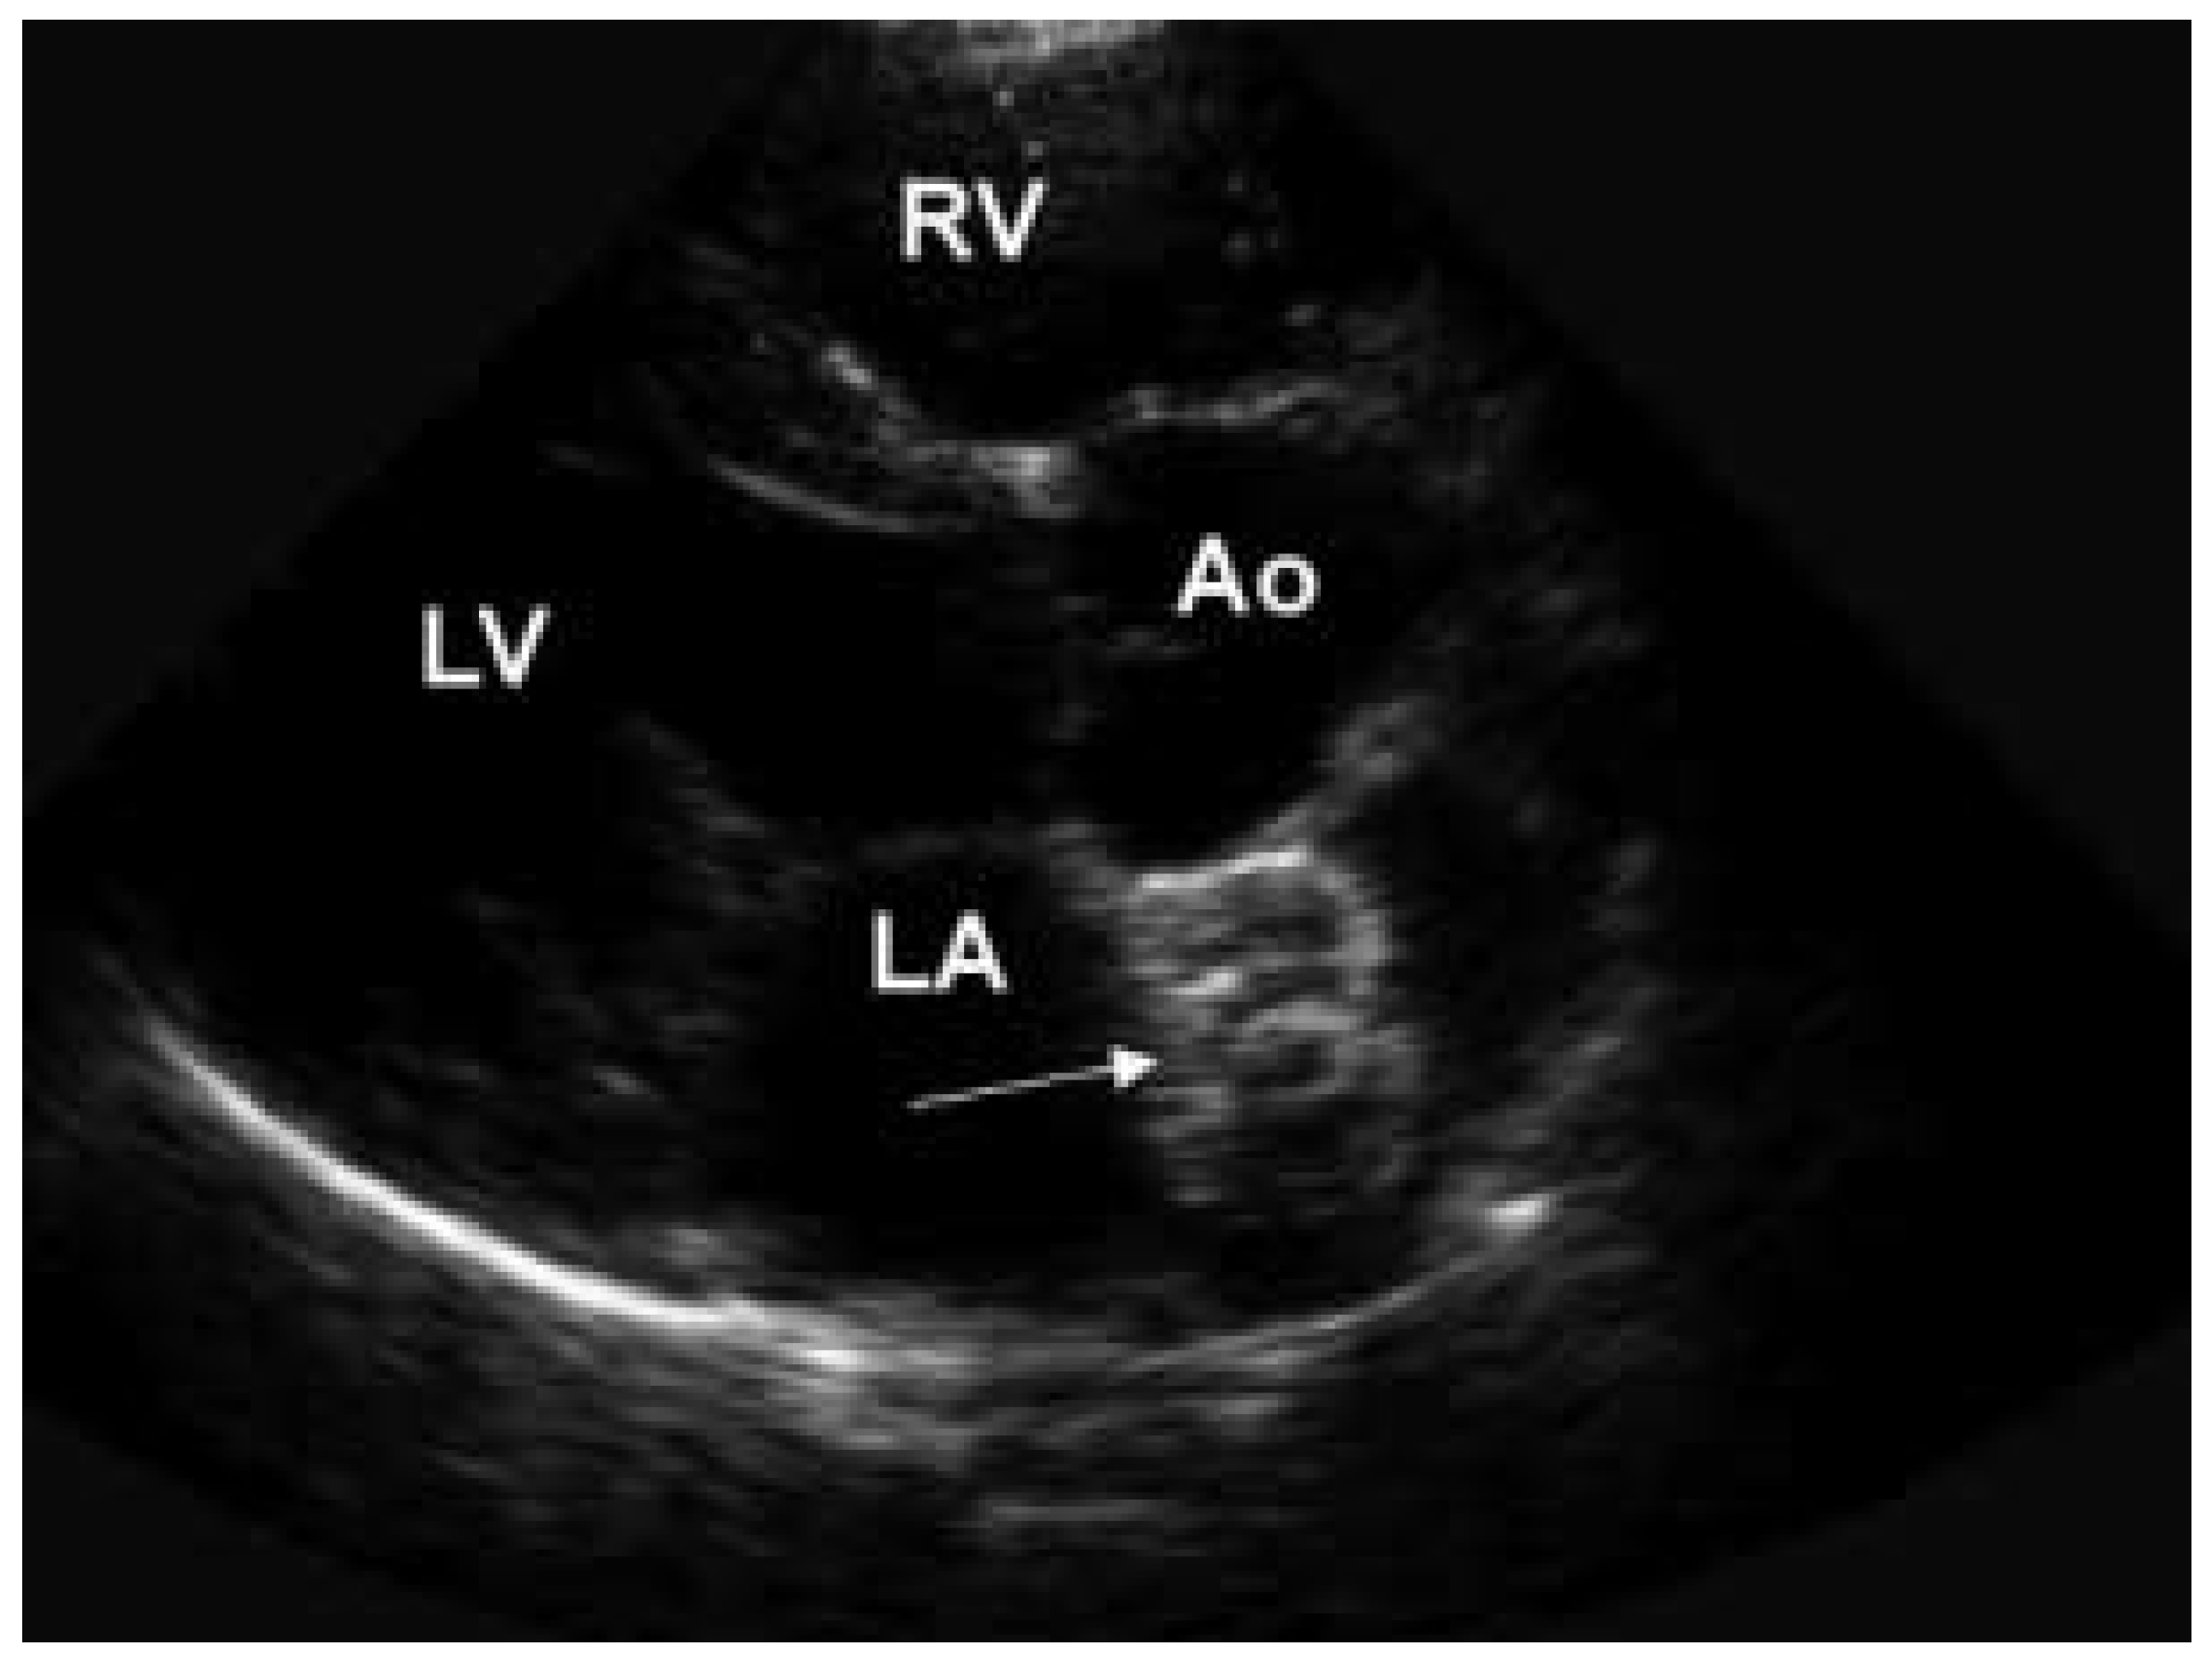

Heutzutage werden alle Arten von Piercing in allen möglichen Körperteilen gefunden. Wir berichten von einer 57jährigen Patientin, bei welcher im Alter von 17 Jahren ein operativer Verschluss eines grossen Vorhof-Septum-Defektes erfolgte. Wegen eines relevanten residuellen Links-Rechts-Shuntes erfolgte aktuell ein invasiver kathetertechnischer Verschluss mittels Amplatzer Okkluder. Die hier präsentierten Bilder wurden anlässlich einer transthorakalen echokardiographischen KontrollUntersuchung drei Monate nach Verschluss des Defektes aufgenommen. Auf dem parasternalen Kurzachsen-Schnitt konnte eine stabile, regelrechte Lage des Amplatzer Okkluder bestätigt werden (Abb. 1a). Ein residueller Links-Rechts-Shunt bestand keiner mehr. Interessanterweise konnte der Amplatzer Okkluder auch auf dem parasternalen Langachsen-Schnitt dargestellt werden, wo er sich wie ein spezielles «atriales Piercing» präsentierte (Abb. 1b). Die drei Ringe entsprechen bei schräger Ansicht den beiden linksund rechts-atrialen Schirmen sowie dem Verbindungsstück des Okkluders.

Abbildung 1b. Parasternaler Langachsen-Schnitt. Pfeil = Amplatzer Okkluder; Ao = Aorta; LA = linker Vorhof; RA = rechter Vorhof; LV = linker Ventrikel; RV = rechter Ventrikel.